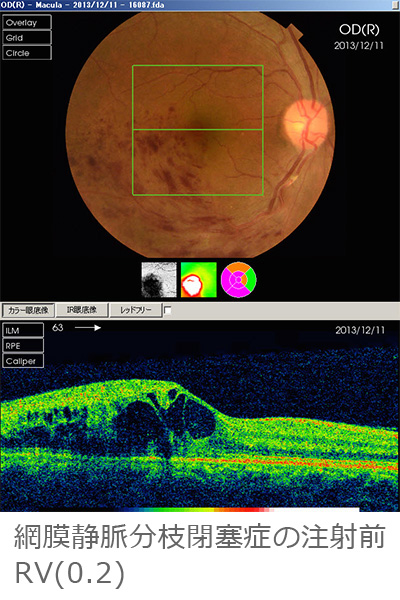

黄斑浮腫に対する抗VEGF療法(ルセンテイス®、アイリーア®)

網膜静脈分枝閉塞症、網膜中心静脈閉塞症による黄斑浮腫、強度近視による脈絡膜新生血管などに対し抗VEGF薬を硝子体注射をすることにより黄斑浮腫を改善することができます。ただ効能があるのが数ヶ月なので、注射を繰り返さざるを得ない症例もあります。注射は一瞬ですが、準備は白内障手術のように厳重に感染を起こさないように行っています。